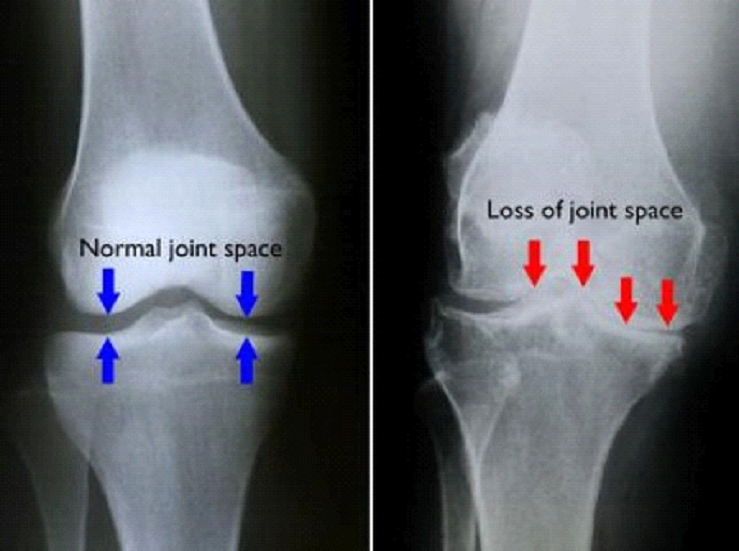

(Left) In this X-ray of a normal knee, the space between the bones indicates healthy cartilage (arrows). (Right) This X-ray of an arthritic knee shows severe loss of joint space.

Knee Osteoarthritis (OA)

What is Knee OA

• Breakdown of cartilage in the knee joint